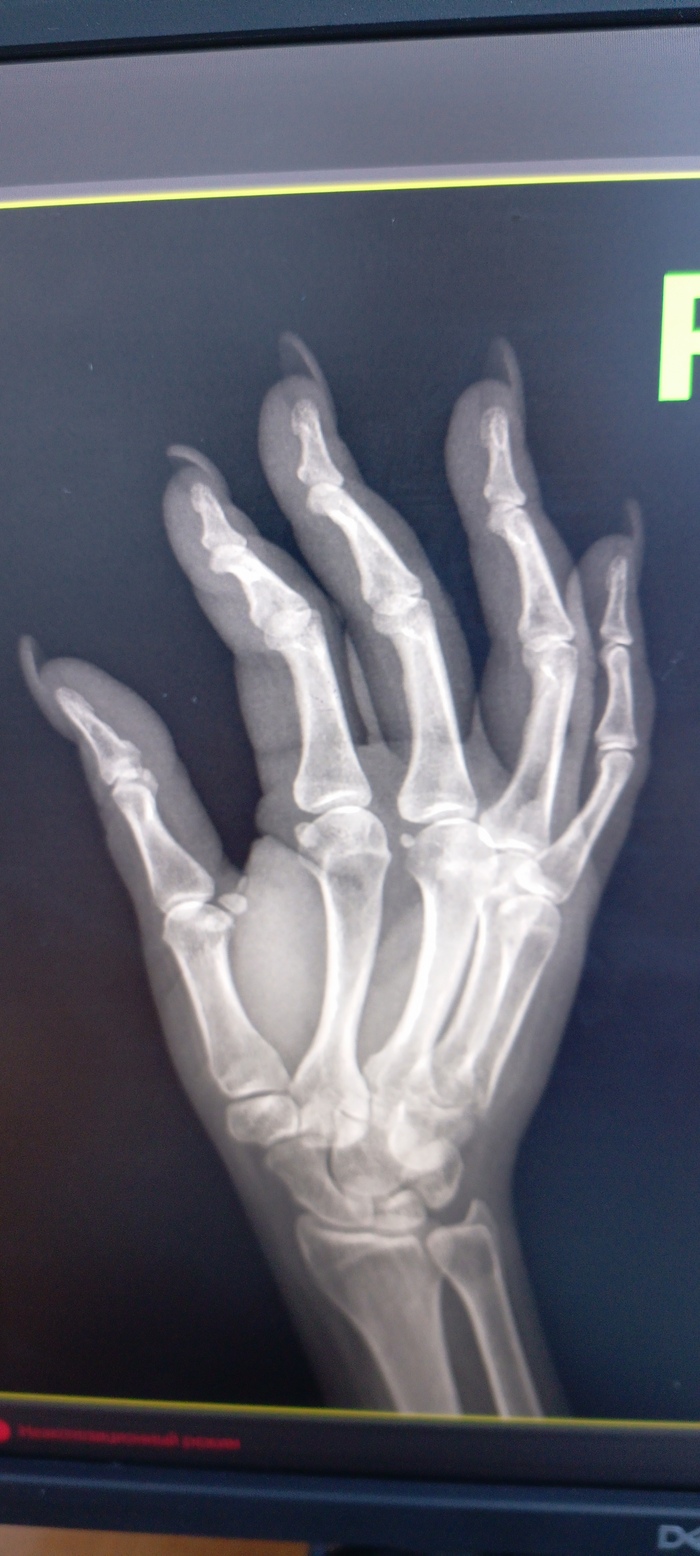

Вышла я на работу. Казалось бы, ну и "чо такова"? А то, что не очень хотелось, то, что я перфекционистка в некоторых моментах... И безотказница. Хотя вот тут такое... Гонялись за мной три месяца. Так уж получилось, что живу в новом регионе России и в связи с этим нюансом могу сказать, что многие медики выехали кто куда(не будем осуждать). Вот и уговорили меня вернуться на прежнее место. Мотивация проста, как два пальца: людей некому лечить, а они болеют. Вышла я значит в ургентный рентген. Ургентный-для ЛЛ- это неотложный. Ну это я так помнила и думала. А вот на деле оказалось, что он ЕДИНСТВЕННЫЙ для всех(город, район. Ургентный и поликлинический). В общем это жопь... С графиком 5/2, с 8 до 14. Я каждый день просто падаю без сил. Ибо за это время я пропускаю через себя от 70 до 120 человек, как повезёт. И я чувствую, что теряю силы... Нет ни перерывов, ни санчаса... Тупо конвейер.